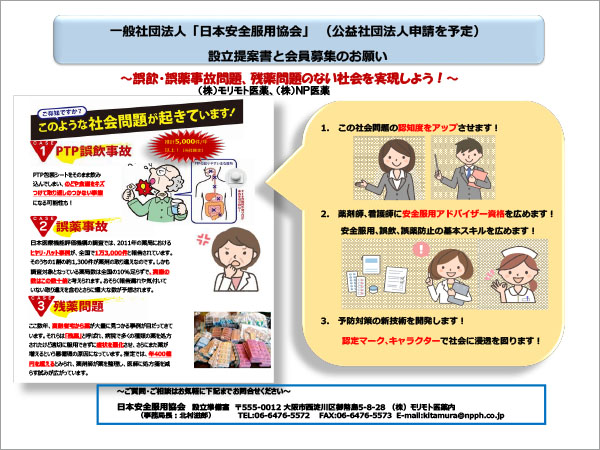

医薬品の 誤飲事故 解決へ 日本安全服用協会 オルタナs Part 2

一般社団法人 日本安全服用協会 Medical Company 58 Photos Facebook